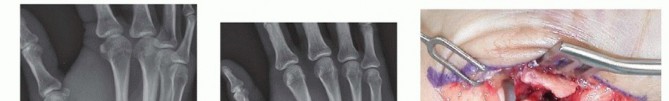

CRPP is the treatment of choice for classic Bennett fractures where the volar-ulnar fragment is too small to reliably accept a lag screw, yet the joint can be anatomically reduced closed. The reduction maneuver is highly specific, designed to counteract the deforming forces of the APL and Adductor Pollicis. Longitudinal traction is applied to the thumb, followed by palmar abduction and pronation. Direct pressure is then applied to the dorsal-radial aspect of the metacarpal base, effectively pushing the shaft back into the anatomic cradle of the intact volar-ulnar fragment.

Once anatomic reduction is confirmed via multi-planar fluoroscopy, percutaneous fixation is achieved. Typically, two 0.045-inch or 0.062-inch Kirschner wires are utilized. The first wire is driven from the dorsal-radial aspect of the metacarpal shaft directly into the trapezium, effectively neutralizing the proximal pull of the APL. A second wire is often placed transversely from the first metacarpal shaft into the second metacarpal to control rotation and maintain the web space. Pins are cut outside the skin and capped to facilitate easy removal in the clinic.

For a large fragment Bennett fracture, the shaft is reduced to the volar-ulnar fragment using a pointed reduction clamp. Provisional fixation is achieved with a K-wire. A 1.5mm or 2.0mm lag screw is then placed perpendicular to the fracture plane. The near cortex must be overdrilled (gliding hole) and the far cortex underdrilled (thread hole) to achieve true interfragmentary compression. The screw head should be countersunk to prevent hardware prominence beneath the thenar muscles.

Fixation Strategies for Rolando and Comminuted Patterns

Rolando fractures present a significantly higher degree of complexity. The classical Y or T pattern often precludes simple lag screw fixation. In these instances, mini-fragment plating is the gold standard. T-plates or specialized condylar plates are contoured to fit the complex geometry of the metacarpal base. The articular fragments are first reduced and provisionally pinned, essentially converting the complex intra-articular fracture into a simpler two-part extra-articular fracture. The plate is then applied to buttress the articular fragments and bridge the metaphyseal comminution to the diaphysis.